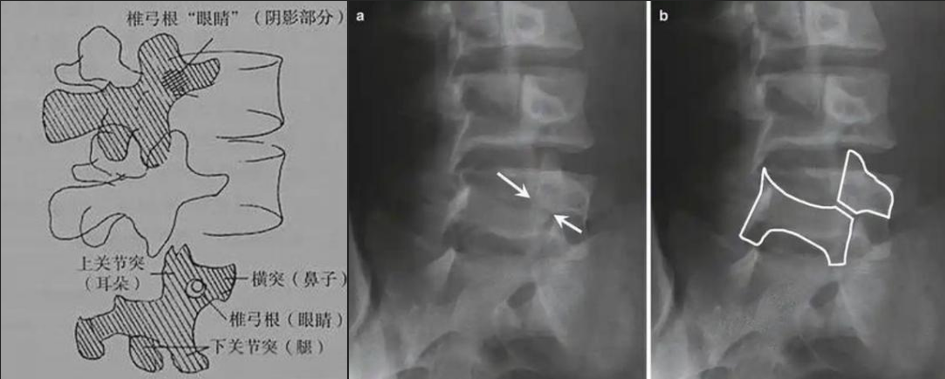

圖a和圖b 腰椎斜位:狗脖“戴項(xiàng)圈征”,診斷椎體椎弓峽部裂

椎弓根峽部是椎體后部椎弓上最狹窄、最薄弱、但應(yīng)力最集中的部位,在常規(guī)腰椎X線(xiàn)正側(cè)位上,因腰椎其他結(jié)構(gòu)的重疊顯示不清,但是在腰椎斜位上,能夠清楚完美地展現(xiàn)出來(lái),若其在斜位片上表現(xiàn)為不連續(xù),則可診斷為椎弓根峽部裂,即腰椎的關(guān)鍵承重部分的骨質(zhì)斷裂,這是導(dǎo)致青少年和運(yùn)動(dòng)員腰痛的主要原因。

在腰椎斜位片上,腰椎的附件結(jié)構(gòu)形成了一個(gè)經(jīng)典的“斯科蒂狗”圖案,其中“狗脖子”處即代表椎弓根峽部,若“狗脖子”上出現(xiàn)了一條透亮清晰的線(xiàn),就像給狗戴了一條“項(xiàng)鏈”,即“戴項(xiàng)圈征”,這是診斷椎弓峽部裂的直接證據(jù)。